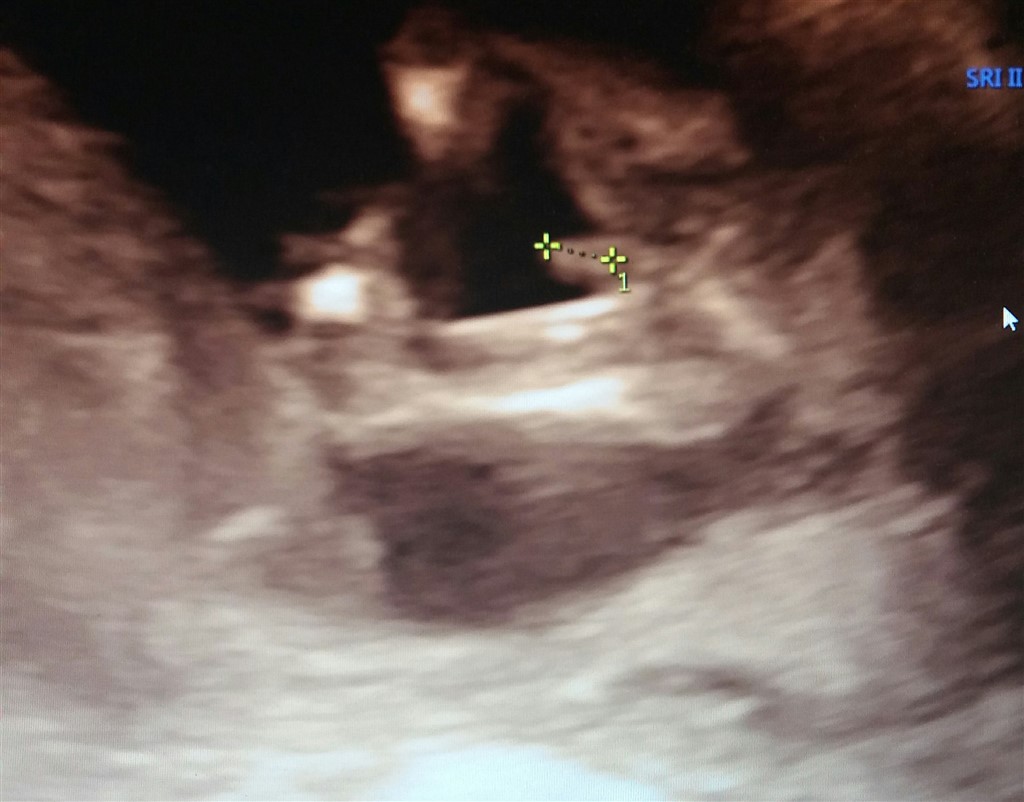

Her er et af vores billeder fra kønsscanningen:

Det er hans tap der bliver målt